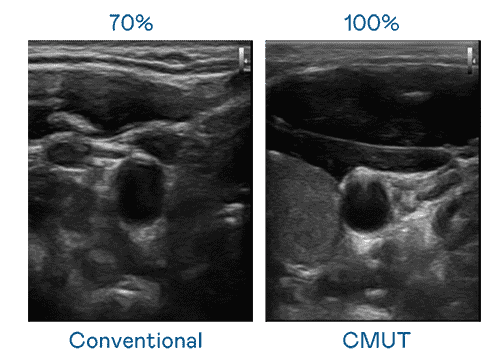

CMUT 技术是一种用电容式微机电元件来产生超音波讯号的技术。。与传统 PZT 压电式技术相比,,,CMUT 频宽增加 30%,,,,更宽频的超音波讯号让影像解析度大幅提升,,,是实现高影像品质医疗超音波扫描、、促进精准医疗发展的关键技术。。。。

大频宽带来超清晰影像

超音波影像的解析度高低,,首先取决于探头能发出的讯号频宽。。赏金国际 CMUT 可提供高清晰的超音波讯号,,,提供高频宽、、、高灵敏度、、影像纹理细节更高的超音波影像,,,协助医护人员缩短影像判读时间及利用精准的医疗影像进行诊断。。。。